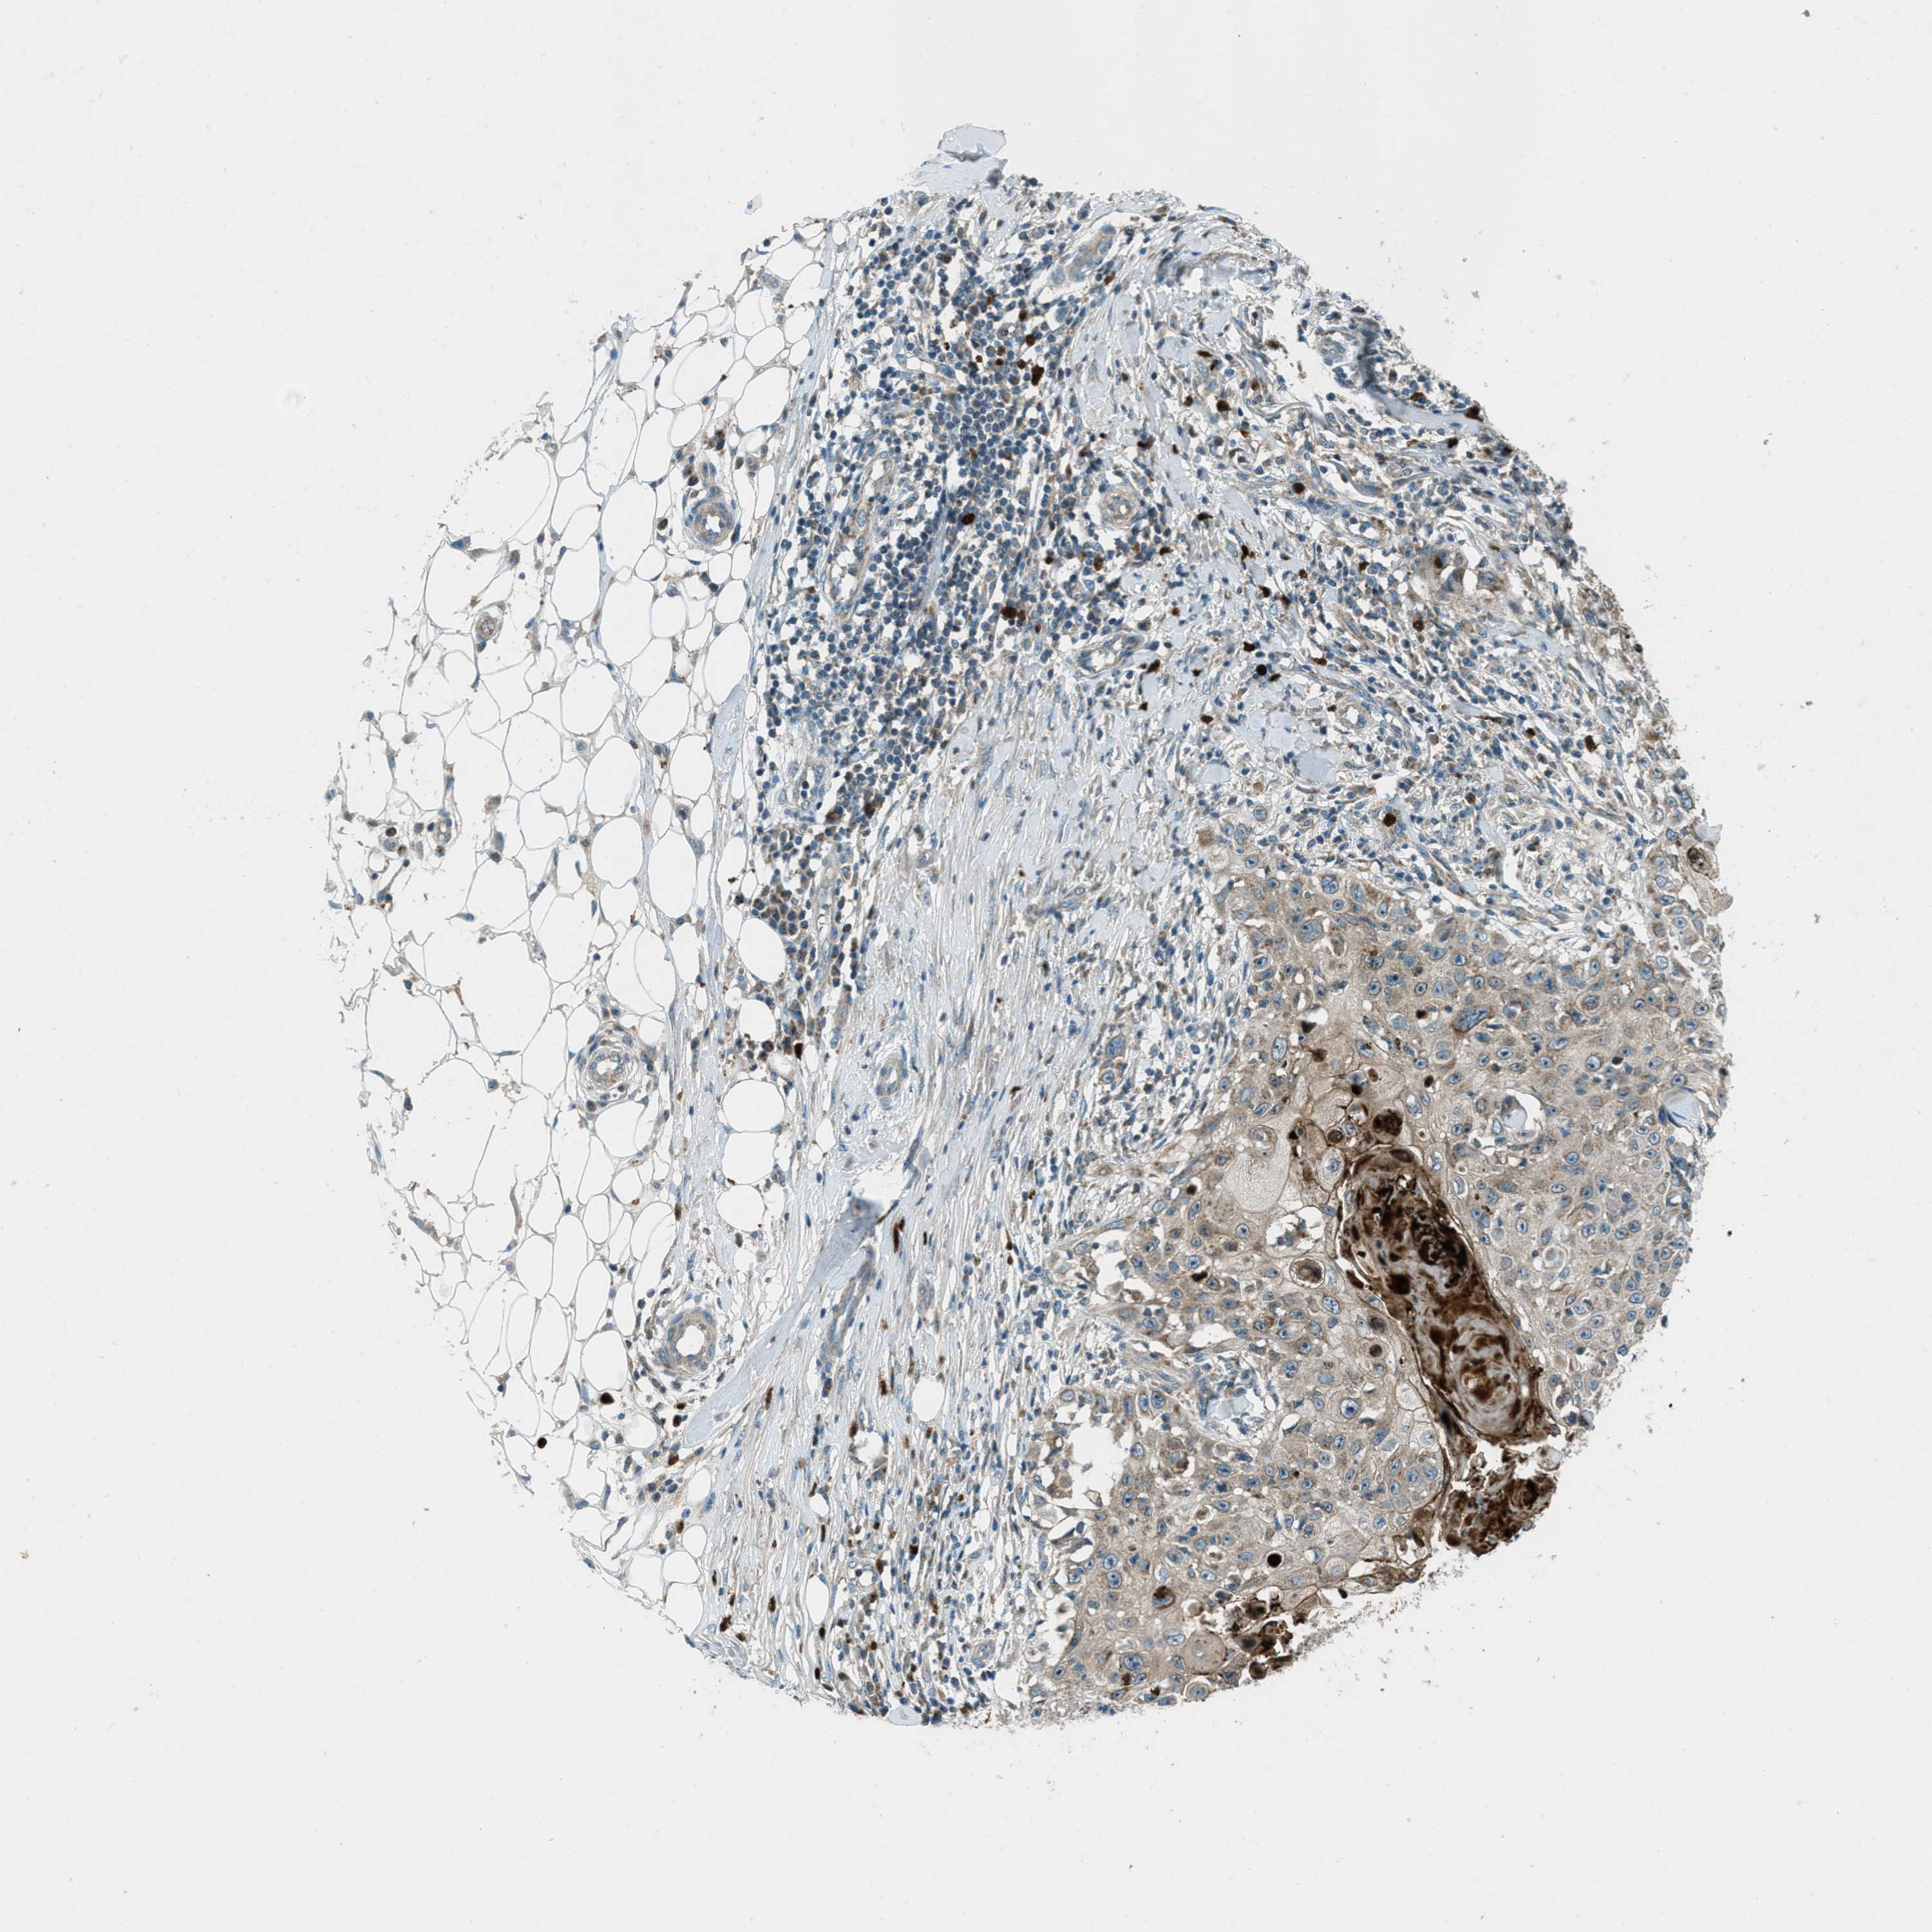

SKIN CANCER - Protein expressioni

A mouse-over function shows sample information and annotation data. Click on an image to view it in a full screen mode. Samples can be filtered based on level of antibody staining by selecting one or several of the following categories: high, medium, low and not detected. The assay and annotation is described here.

Antibody stainingi

Antibody staining in the annotated cell types in the current human tissue is reported as not detected, low, medium, or high, based on conventional immunohistochemistry profiling in selected tissues. This score is based on the combination of the staining intensity and fraction of stained cells.

Each image is clickable and will lead to virtual microscopy that enables deeper exploration of all samples and also displays staining intensity scores, fraction scores and subcellular localization as well as patient and tissue information for each sample.

Antibody HPA017322

Staining

High

Medium

Low

Not detected

Intensity

Strong

Moderate

Weak

Negative

Quantity

>75%

75%-25%

<25%

None

Location

Nuclear

Cytoplasmic/membranous

Cytoplasmic/membranous,nuclear

Squamous cell carcinoma in situ, NOS